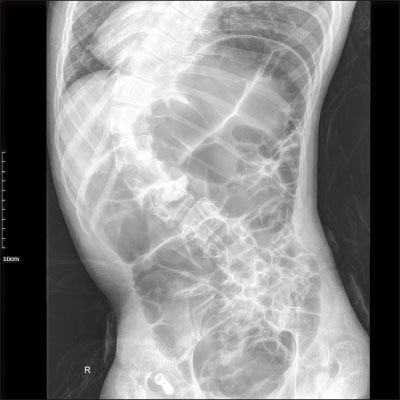

During laparoscopic exploration, adhesion of the transverse colon to the stomach wall of the gastrostomy site was seen and appeared twisted (

Fig. 3). Proximal transverse colon was redundant and upstream dilatation from the twisted transverse colon to the ascending colon and the cecum was found with reversed intestinal anatomy, as identified on preoperative images. Sigmoid colon was collapsed and not redundant, so the suspicious sites of endoscopy were not related to the symptoms. Adhesiolysis and fibrous band lysis between the transverse colon and adherent soft tissue was done. Redundant proximal transverse colon was resected via mini-laparotomy site, and end-to-end colocolic anastomosis was performed (

Fig. 3Adhesion of transverse colon on stomach wall and twisting (arrow) with upstream colon dilatation (arrowhead).